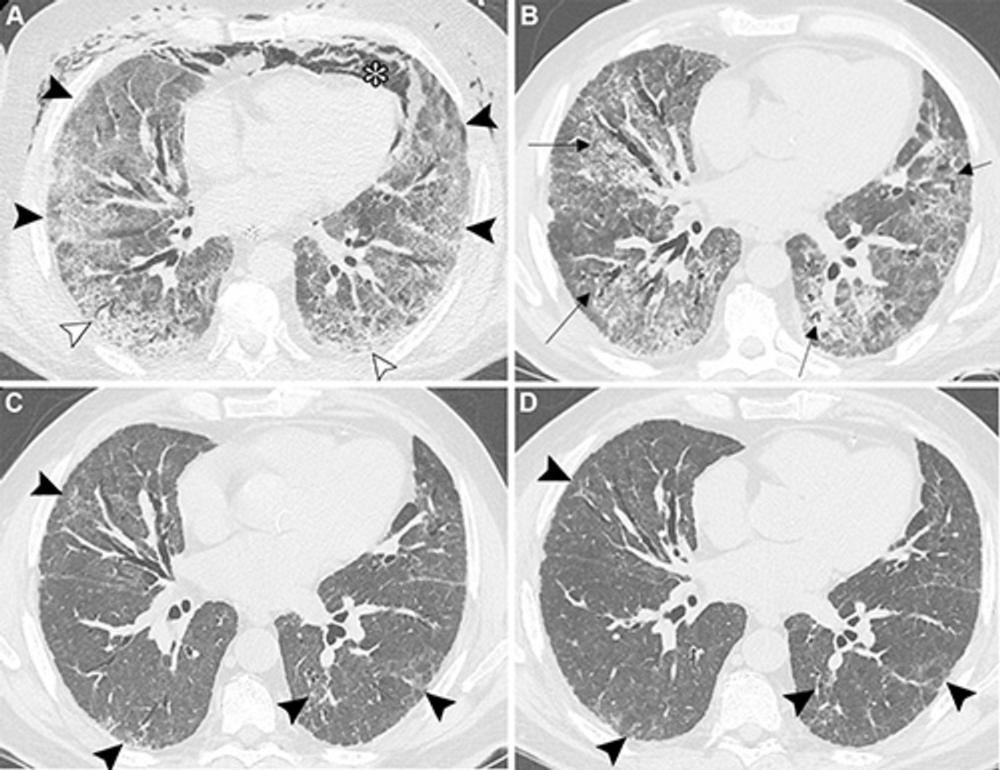

Figure 4. Unenhanced axial CT images show (A, B) post–COVID-19 residual lung abnormalities in a 70-year-old female patient and (C, D) fibrotic interstitial lung abnormalities in a 63-year-old female patient. (A) Image at the carina level obtained at 15-month follow-up shows post–COVID-19 multifocal faint ground-glass opacities and mosaic attenuation in the upper lobes (arrowheads). (B) Image shows parenchymal band (arrows) in the right lower lobe and perilobular opacities along the peribronchovascular and subpleural areas of the left lower lobe (oval dotted line). Parenchymal bands and perilobular opacities are unusual in interstitial lung abnormalities and support the diagnosis of post–COVID-19 residual organizing pneumonia. (C) Image obtained in 2019 shows fibrotic interstitial lung abnormalities. The image at the carina level shows minimal subpleural linear opacities in the upper lobes and superior segment of the left lower lobe (arrows). (D) Image shows juxtapleural reticular opacities, traction bronchiolectasis, and ground-glass opacities, primarily involving both lower lobes (arrowheads).